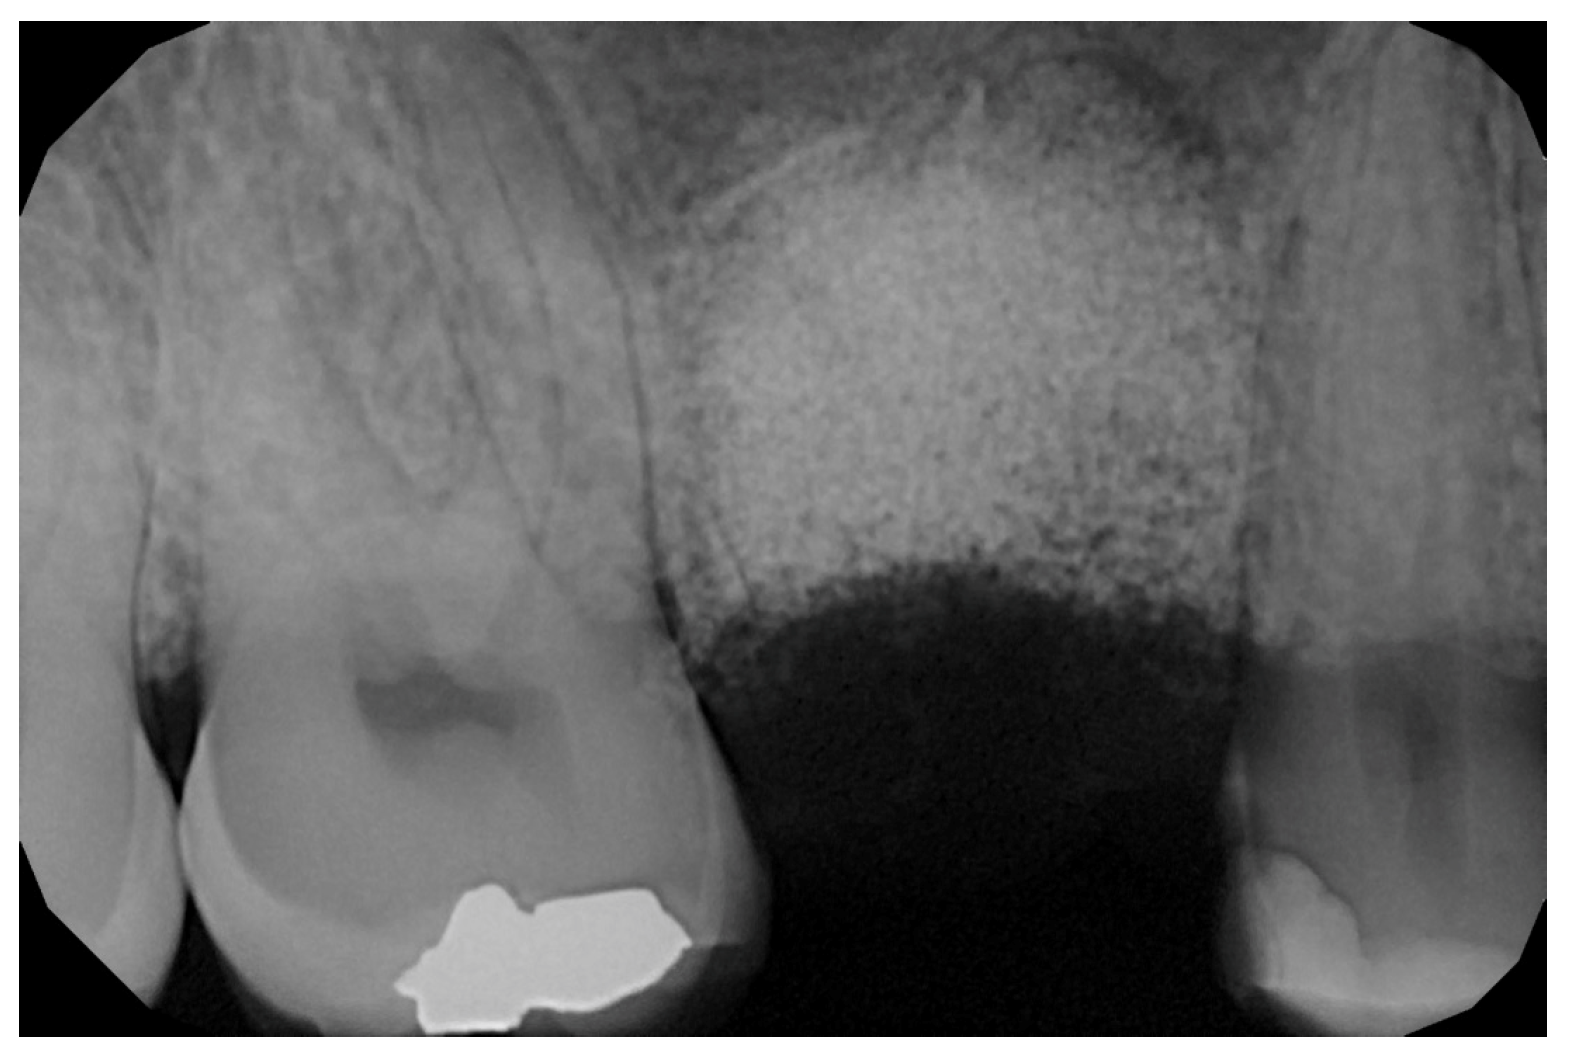

2.6. Case Presentation. Nano-HA Applied to Socket Preservation Procedures

3. Results